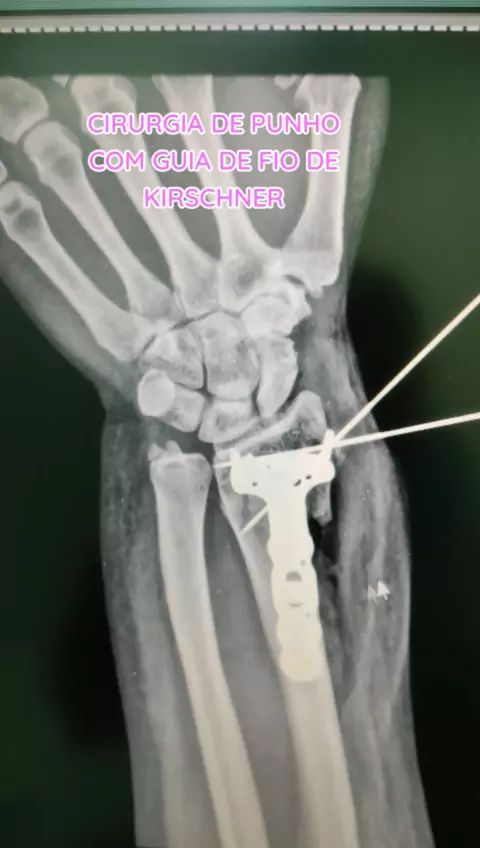

DANILO SALES NEVES